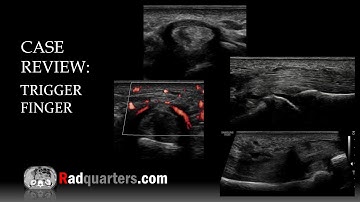

Trigger finger - a unique Ultrasound feature